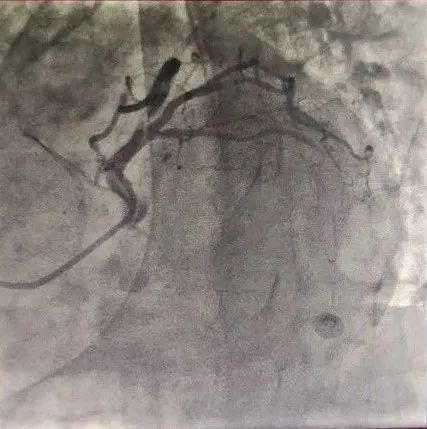

病例三

患者为78岁女性,主因间断胸闷3年就诊,冠状动脉CTA提示冠状动脉严重钙化,左主干管壁多发钙化,管腔狭窄,前降支严重钙化伴管腔狭窄大于70%,回旋支严重钙化伴有管腔严重狭窄。由于钙化严重,术前刘巍主任团队就做好了充分的准备。冠状动脉造影提示左前降支严重钙化伴有多发斑块管腔偏细,回旋支远段85%狭窄,右冠状动脉全程钙化伴有多发斑块。计划使用IVUS对回旋支狭窄进行评估,但IVUS无法通过近段病变,IVUS提示近段钙化角度大于270°。刘巍主任使用1.25mm磨头对回旋支进行旋磨,旋磨后,球囊及IVUS可顺利通过钙化病变到达远端,IVUS提示管腔弥漫性斑块,斑块负荷重,远段管腔严重狭窄,刘巍主任决定植入支架,经旋磨后,支架可顺利通过钙化病变部位,成功释放,支架膨胀效果良好。术后患者胸闷明显缓解。

冠脉CTA显示LCX狭窄伴钙化

对LCX进行旋磨术

LCX血管狭窄明显改善